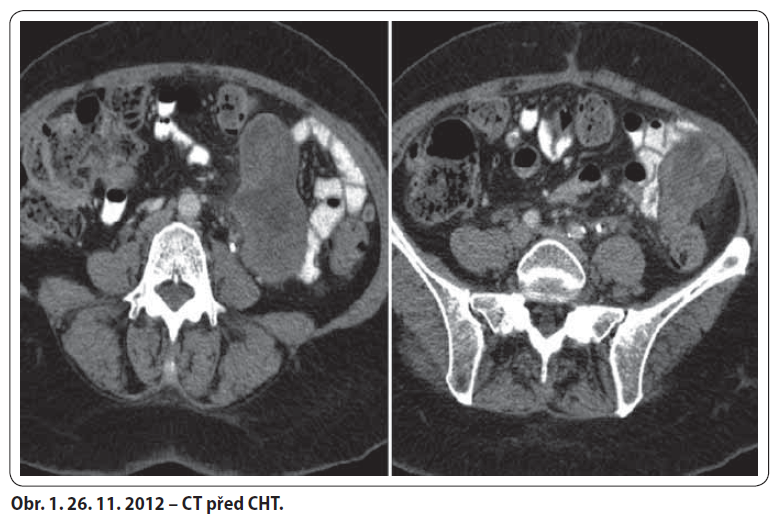

57letá žena, bez komorbidit a chronické medikace, došetřována od ledna 2012 pro chřipkové příznaky a váhový úbytek 10 kg. Proveden UZ břicha a gynekologické vyšetření s nálezem hypoechogenního útvaru v malé pánvi. Následně laparotomie s ovarektomií, kde v oblasti levé ovariální fosy tumor retroperitonea fi xující levý vaječník a vejcovod, potvrzeno i na CT. Histologicky dobře diferencovaný smíšený mezenchymální maligní tumor. 19. 7. 2012 v MOÚ Brno exstirpace nejasně ohraničeného tumoru (130 × 100 × 80 mm) spolu s hysterektomií. Histologicky high-grade polymorfocelulární sarkom bez bližší orgánové specifikace. Následně adjuvantní RT v KOC Zlín v dávce 46,8 Gy/ 26 fr. na malou pánev a 59,4 Gy/ 33 fr. na lůžko tumoru. Po ukončení RT pro bolesti zad provedeno CT. Na něm nově objemné expanzivní útvary mezi střevními kličkami a v levém mezogastriu – suspektní metastázy. V 1/ 2013 revize dutiny břišní v MOÚ Brno – nález inoperabilní, provedena paliativní spojková operace a vyvedena ileostomie. U pacientky s dobrým PS tedy indikována první linie paliativní CHT Adriamycin 3W. Od 2/ 2013 do 6/ 2013 bylo podáno celkem šest sérií se zajištěním filgrastimem pro neutropenie grade III. Dle CT přešetření bylo dosaženo parciální odpovědi. Z onkochirurgické komise KNTB pacientka indikována k operačnímu výkonu. 20. 8. 2013 byla provedena maximální debulking operace. Pooperačně CT i PET/ CT negativní. Poté podány tři série zajišťovací chemoterapie Adriamycin 3W s profylaktickým podáním filgrastimu. Kontrolní CT bez známek recidivy tumoru. V 3/ 2014 zanoření ileostomie. Dle CT restagingu z 5/ 2014 a 11/ 2014 trvá kompletní odpověď.